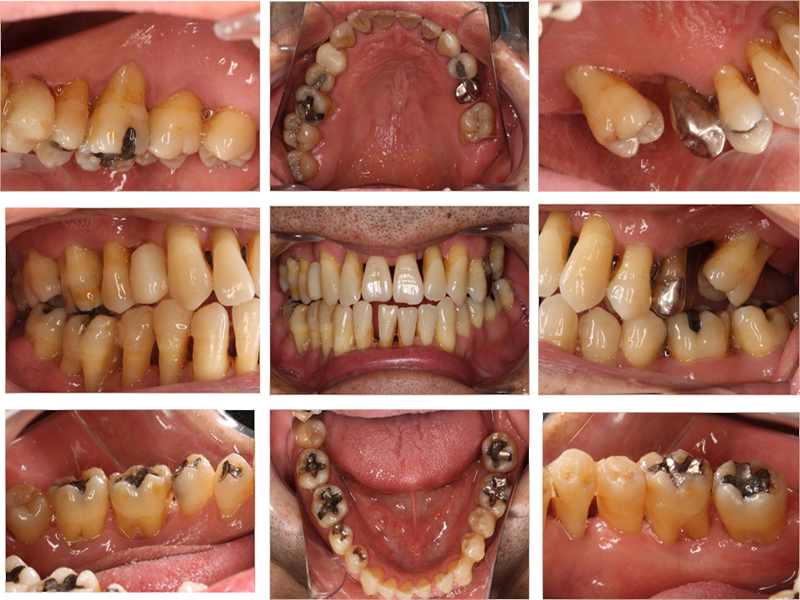

初診時口腔内写真

初診時X線写真